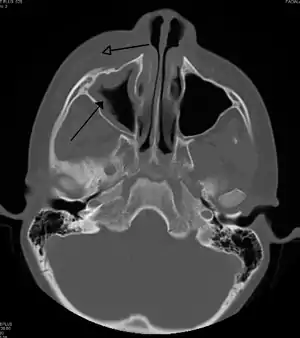

CT of chronic sinusitis

CT scan of chronic sinusitis, showing a filled right maxillary sinus with sclerotic thickened bone.